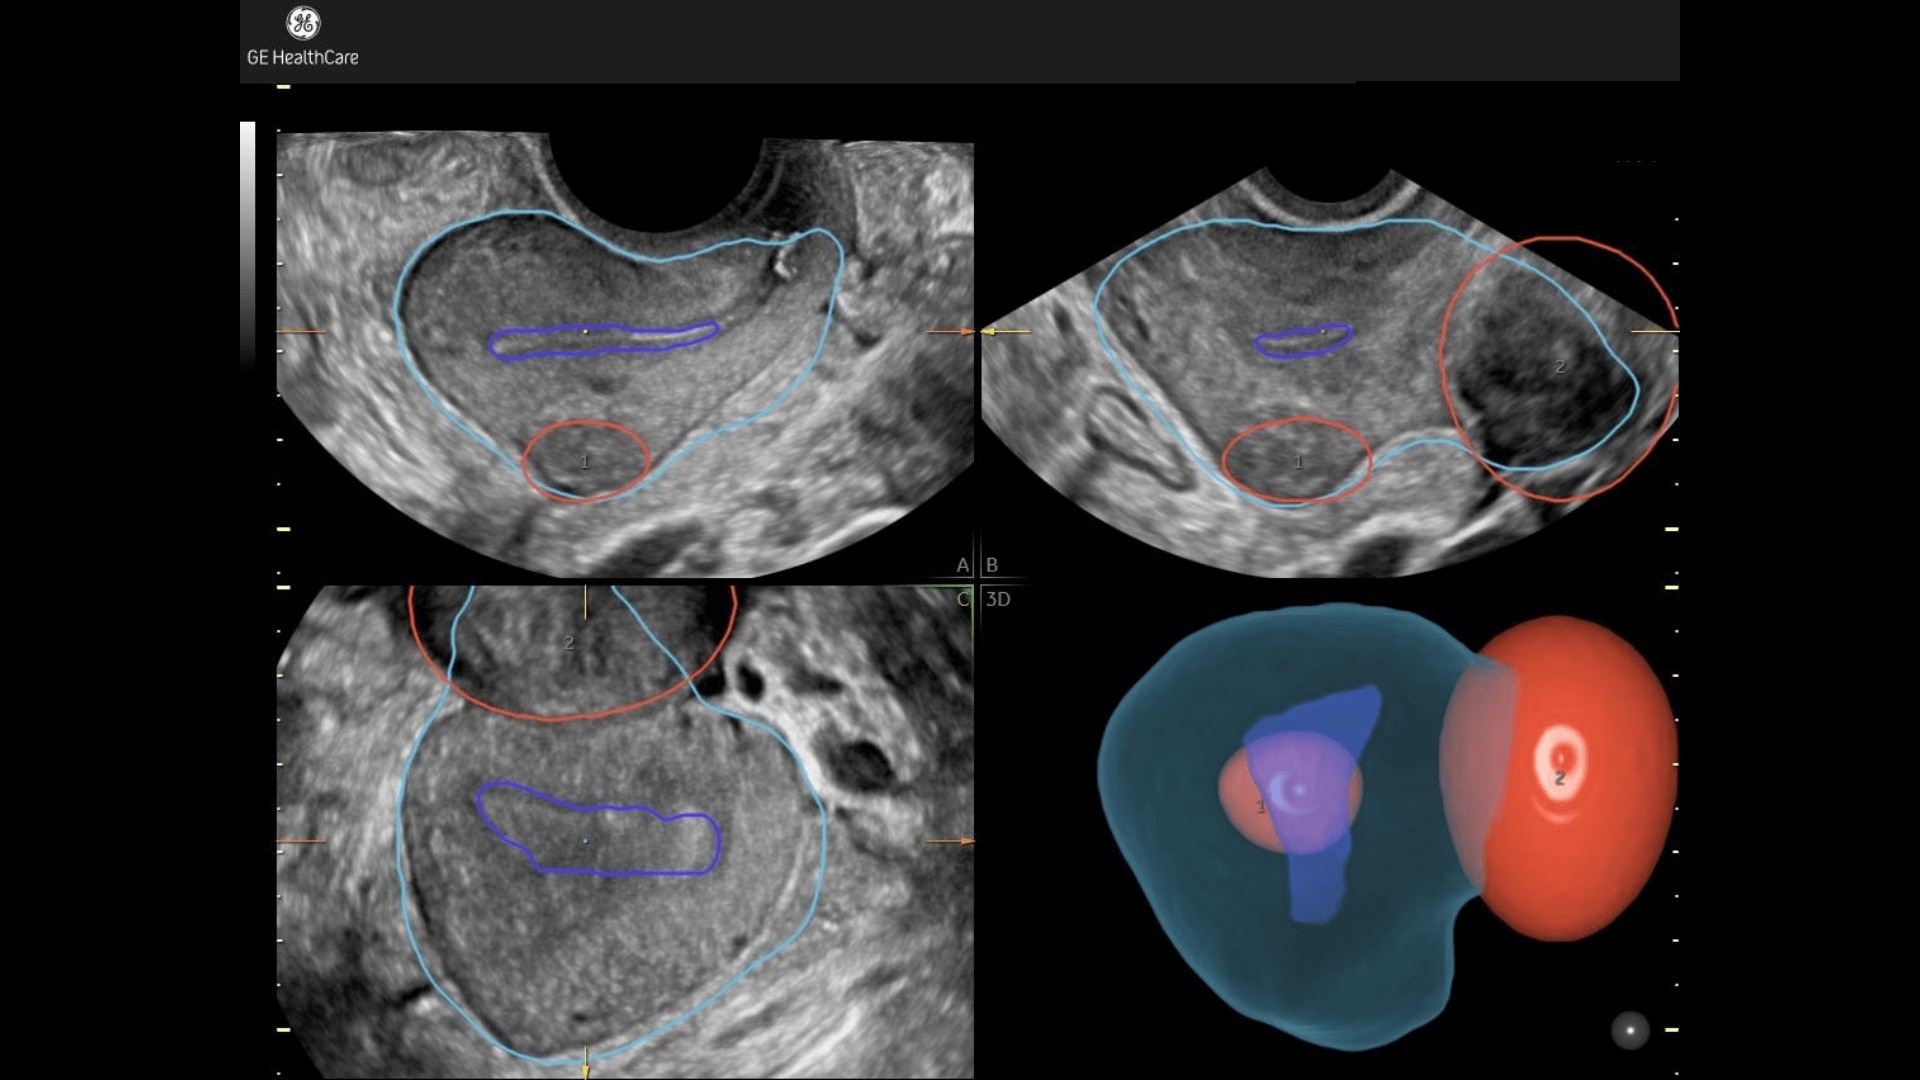

Fibroid Mapping

Uterine fibroid location & size highlighted in 3D.

Uterine fibroid location & size highlighted in 3D

• Illustrates position of fibroid in relation to uterus in 3D.

• Classify each fibroid according to FIGO© classification.

• Simplify communication with colleagues, referring pysicians and patient.